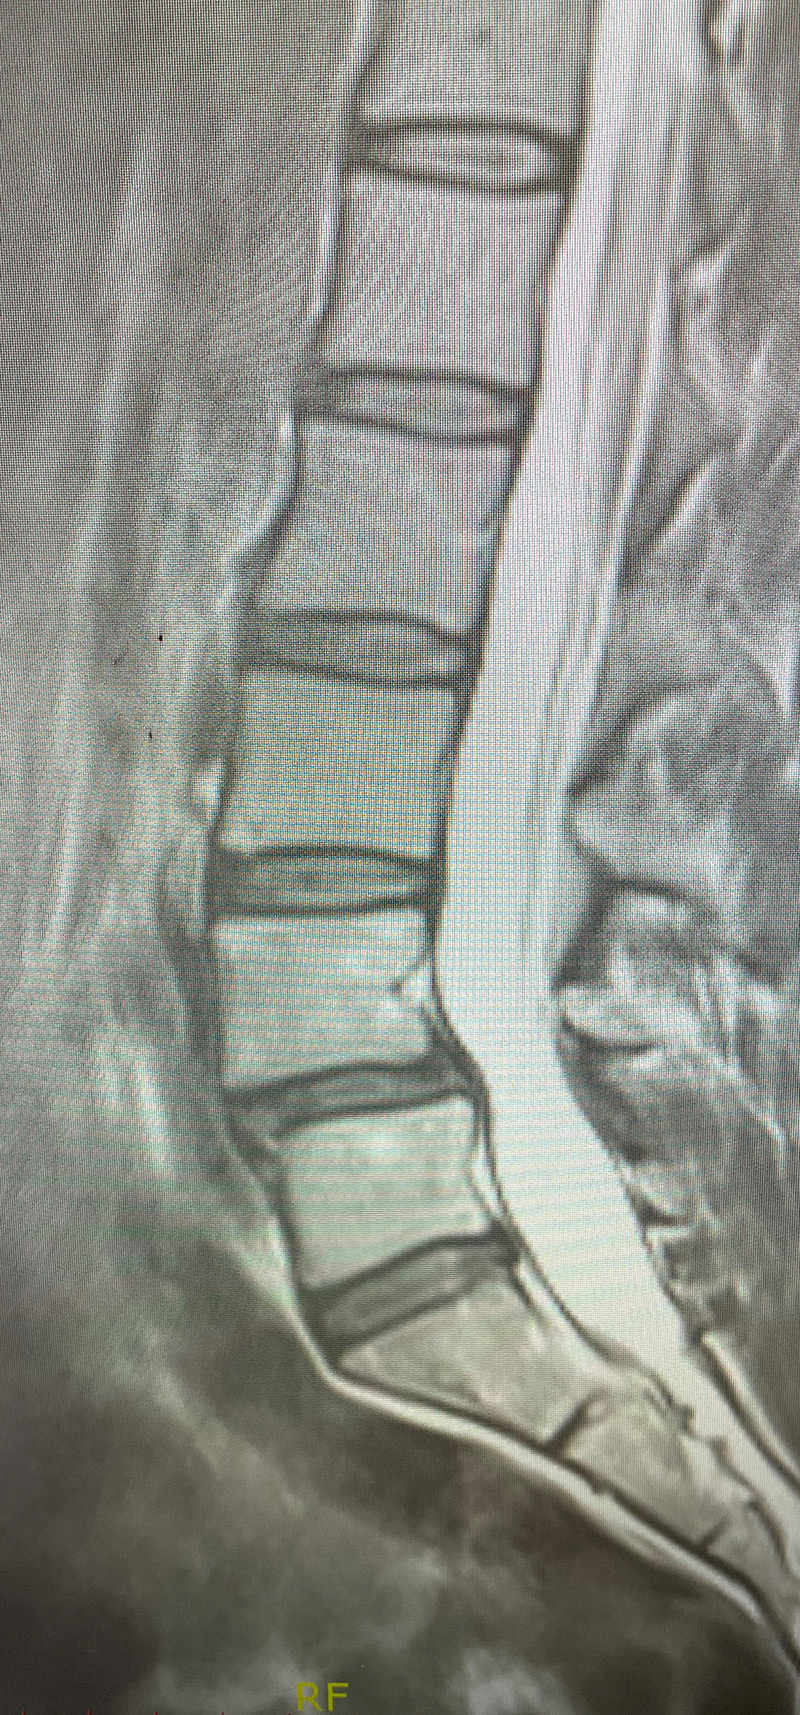

This 42-year-old female presents with ten years of progressive low back pain and leg pain. She had mild left dorsiflexion and EHL weakness. She had tried physical therapy, but her symptoms persisted. MRI revealed an L4-5 grade 1 spondylolisthesis with stenosis (Fig 1). We discussed options. We decided to try an epidural injection and continue with physical therapy. She will follow up with me in 6-8 weeks to see how she is doing with her pain and strength.

An L3-5 laminectomy would be offered with an extensive facetectomy to fully decompress bilaterally her L4 and L5 nerve roots and perform a posterolateral fusion with titanium screws to fixate her level to prevent further instability and to prevent recurrent stenosis. Because of her relative disc height loss and to provide more stability, an interbody spacer would provide the best restoration of her anatomy, disc height, and by distracting the interspace, improve foraminal dimensions.